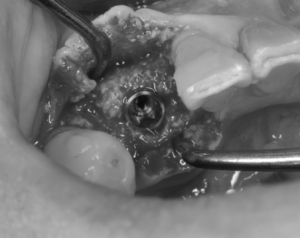

インプラントのシミュレーションからガイドを制作しインプラントを設置していきます。

その後、骨が少ないと予測されていた部位に自家骨、異種骨を足して、メンブレンという膜にて覆います。

メンブレンという膜にて覆います。

最後に歯肉に無理な力がかからないようにテンションフリーにて縫合して終了です。

おおよそ30分ほどの治療内容です。(骨の造成がなければ10〜15分程度です)